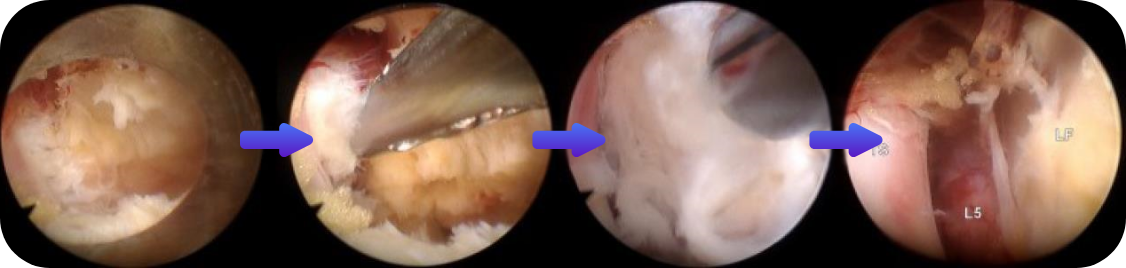

이 수술법이 처음 나온 지는 20년이 넘었습니다만 최근 들어 기기와 기술의 발전으로 각광을 받게 되었습니다. 피부에 약 7 mm 크기의 내시경을 넣어 수술을 하는 것으로 수술 후 회복이 매우 빠르다는 장점이 있습니다. 과거에는 터져 나온 디스크를 처리하지 못하는 한계를 보였으나 이제는 많이 발전하여 디스크의 여러 유형을 처리할 수 있어 수술의 성공률이나 환자의 만족도도 많이 높아졌습니다.

- 추간판탈출증